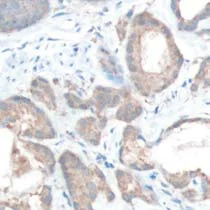

Immunohistochemical analysis of formalin fixed, paraffin embedded Human prostate adenocarcinoma tissue labelling MAP4K4 with ab150300 at 1/100 dilution.This data was developed using the same antibody clone in a different buffer formulation containing PBS, BSA, and sodium azide (ab150300)

Immunohistochemistry (Formalin/PFA-fixed paraffin-embedded sections) - Anti-MAP4K4/NIK antibody [SP177] - BSA and Azide free (AB245752)

Immunohistochemical analysis of formalin fixed, paraffin embedded Human prostate adenocarcinoma tissue labelling MAP4K4/NIK with ab150300 at 1/100 dilution.

This data was developed using the same antibody clone in a different buffer formulation containing PBS, BSA and sodium azide (ab150300).